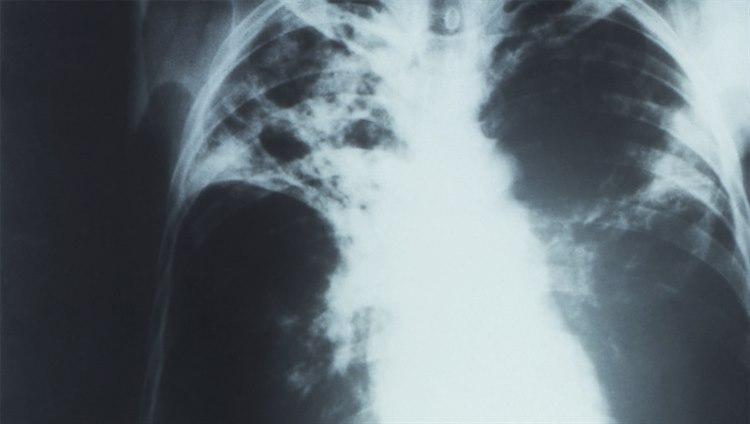

Kostbar og tidkrevende behandling

Foto: PHIL - CDC: Røntgenbilde (anterioposteriort) av en pasient med diagnosen avansert, aktiv, lungetuberkulose. Bildet viser bilateralt infiltrat og typisk tuberkulose-uthuling av høyre lungetopp.Antibiotikaresistent tuberkulose er både vanskeligere og dyrere å behandle enn vanlig tuberkulose. Den er også mer dødelig. Behandling av resistente tuberkulosebakterier er svært kostbart - opptil 200 ganger dyrere enn vanlig tuberkulosebehandling. Behandlingen i seg selv kan også gi alvorlige bivirkninger.